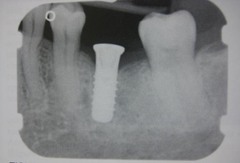

implant

Front

Back